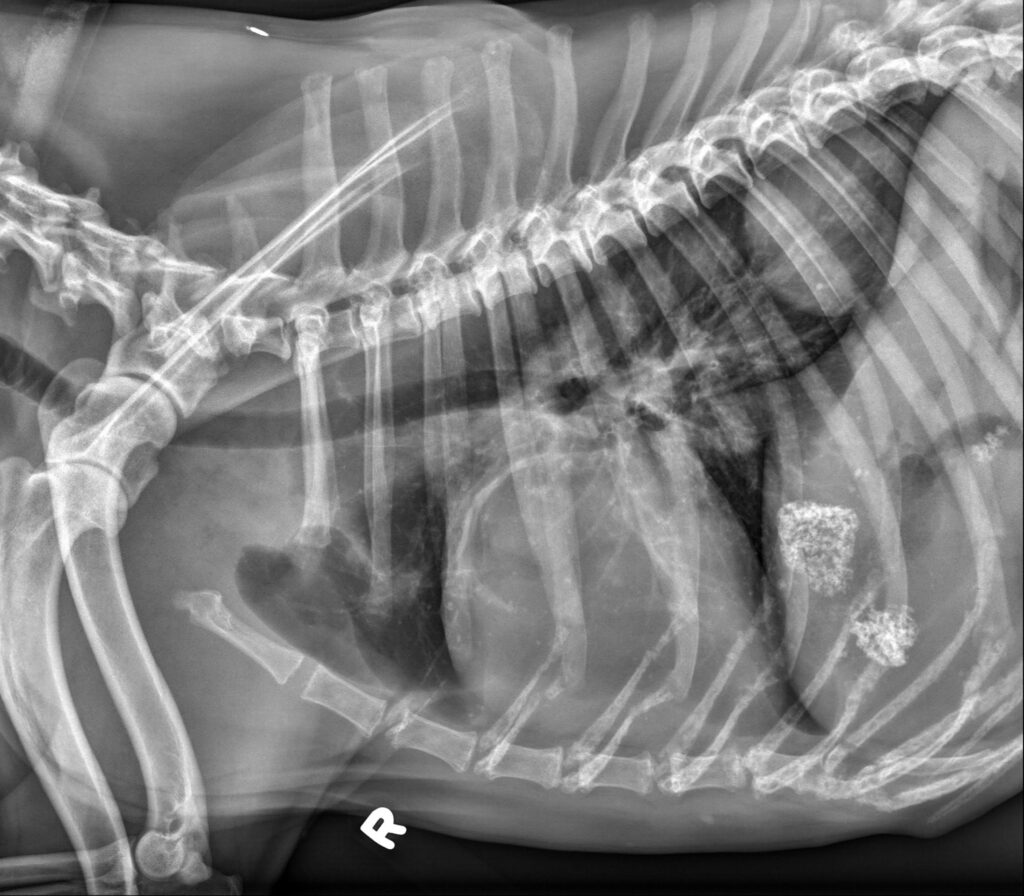

Radiology Quiz August 2025

History 13 year old female spayed cat. Anorexia. Peridontal disease.